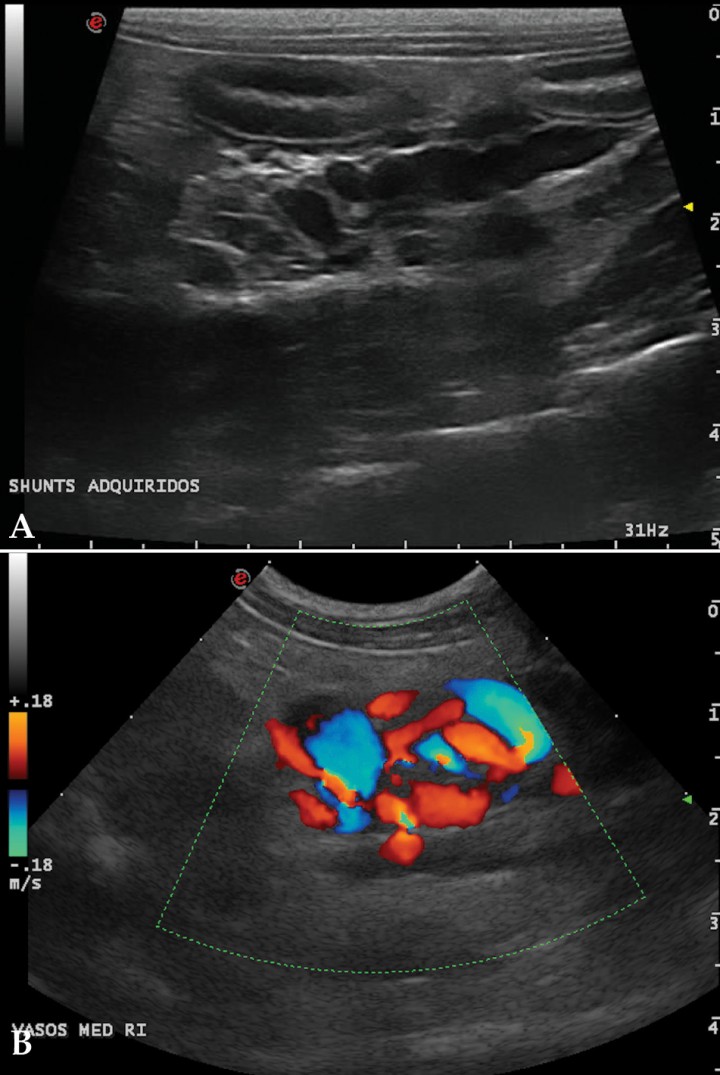

La ecografía hepática mostro un hígado de pequeño tamaño, con presencia de focos hiperecoicos y con sombra acústica (Fig. 2). Los conductos biliares mostraban distensión severa y aspecto tortuoso, manteniendo su comunicación con la vesícula biliar, sin evidencia de obstrucción en algún punto concreto de su recorrido (Fig. 3). La papila duodenal se visualizaba normal. La vena porta presentaba pequeño tamaño, flujo hepatópeto y velocidad aparentemente reducida (Fig. 4). Se evidenció la presencia de múltiples vasos de aspecto tortuoso adyacentes al riñón izquierdo (Fig. 5). Ambos riñones presentan múltiples infartos renales y focos mineralizados en la corteza, sedimento con sombra acústica en pelvis renal izquierda y presencia de cálculos en riñón derecho (Fig. 6). Pequeña cantidad de líquido libre anecoico (Fig. 7).

<p>(A) Corte longitudinal, medial al riñón izquierdo. Múltiples vasos sanguíneos distendidos y tortuosos compatibles con shunts portosistémicos extrahepáticos adquiridos. (B) Corte longitudinal, medial al riñón izquierdo. Detalle Doppler color.</p>

Figura 5

(A) Corte longitudinal, medial al riñón izquierdo. Múltiples vasos sanguíneos distendidos y tortuosos compatibles con shunts portosistémicos extrahepáticos adquiridos. (B) Corte longitudinal, medial al riñón izquierdo. Detalle Doppler color.

En perros, las comunicaciones múltiples son comúnmente esplénicas, y se presentan en el área perirrenal izquierda y la raíz del mesenterio (Fig. 5). Esto es debido a que el incremento de la resistencia al flujo sanguíneo portal determina que las conexiones microvasculares no funcionales, presentes al nacimiento entre la vena porta y las vías sistémicas, se tornen funcionales, de manera que las comunicaciones portosistémicas representan dilataciones adquiridas de comunicaciones microvasculares normales entre la vena porta y las venas sistémicas.

En nuestro paciente (Figs. 4, 5 y 7) la presencia de estos shunts múltiples, junto con el perfil de flujo portal y la presencia de ascitis, son altamente sugerentes de que el proceso de base está provocando HTP.